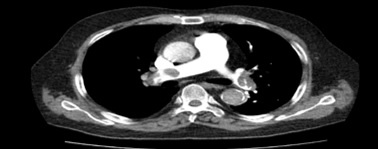

Hình ảnh huyết khối lớn động mạch phổi hai bên. Ảnh: BSCC.

Ngoài ra, một số trường hợp thuyên tắc phổi xảy ra sau 3 tháng ở trường hợp mắc Covid-19 mức độ nhẹ. Thuyên tắc phổi là biểu hiện nghiêm trọng nhất của thuyên tắc huyết khối tĩnh mạch, liên quan tỷ lệ tử vong cao ngay tại thời điểm được chẩn đoán hoặc trong vài giờ sau đó.

Đến nay, thuyên tắc phổi (PE) vẫn là mối quan tâm lớn về sức khỏe trên toàn thế giới. Đây là nguyên nhân tim mạch gây tử vong thứ 3 sau nhồi máu cơ tim và đột quỵ. Bệnh lý thuyên tắc phổi trong bối cảnh dịch Covid-19 càng làm gia tăng tỷ lệ mắc, tử vong và nhập ICU.